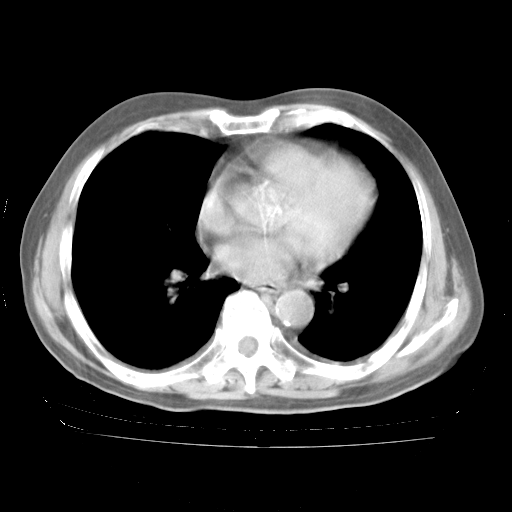

4月28日肺部CT——再次出现类似去年5月9日——透光度降低,“间质性”改变。

4月28日肺部CT

个人阅读4.14日肺部CT平扫:纵隔窗无异常,但肺窗示:双下肺内、后基底段有片絮状侵润影,部位以后基底段为著,以间质改变为主,呈急性肺泡炎征像,和首次住院影像学有相似之处。仅是个人读片,明日请相关专家再读片哈。其它建议同上。

1、108#的是4月14日的胸部CT(发此贴时还没看着28日的CT)。14日的胸部CT其实已经出现改变(如108#所述),个人认为28日的胸部CT除纵膈窗疑似有双侧胸膜增厚或少量胸积液(可行胸部B超明确)外,与4月14日对照病变有所加重;2、已经给予“异烟肼、利福平、乙胺丁醇”抗痨治疗?如果是,甲强龙80mg可缓慢减量;如果环磷酰胺已停用,暂不使用;3、中性粒细胞92%,明显升高,目前体温情况?注意合并细菌感染可能,使用左氧氟沙星情况下,是否联用B-内酰胺类抗菌药物?另外是查免疫全套非风湿全套。

今请临免主任会诊后认为:4月14日胸部CT已有双下肺间质性改变。患者病情复发多系激素减量过快不正规所致。目前甲强龙80mg/日,一周后酌情开始减量,不易过快。环磷酰胺若已停用,暂不使用。他同意目前抗菌药物使用,但应考虑是否加用B-内酰胺类抗菌药物(中性细胞明显增高);2、结核复发目前依据不足;3、若免疫全套各项指标正常,考虑多系特发性肺间质炎可能大。4、加强支持,并注意保护胃黏膜。

今上午去请教了临免、呼吸主任:1、介绍病史和阅读系列胸部CT一致认为:患者肺结核不考虑,仍为肺间质纤维化,目前处于急性肺泡炎阶段。2、若仍发热,可将甲强龙增至:80mg Bid静滴,同时鉴于中性增高,合并细菌感染可能,继续左氧氟沙星治疗,再联用B-内酰胺抗菌药物,如头孢哌酮--舒巴坦;3、停用抗痨药;4、目前甲强龙每日剂量160mg ,体温正常后再酌情减量;目前暂不用免疫抑制剂;4、不建议使用免疫增强剂等;5、加强支持治疗,鼓励患者进食;5、注意随访肝、肾功及血常规情况;6、因患者目前激素用量较大,加用胃黏膜保护剂,防止消化道出血可能。